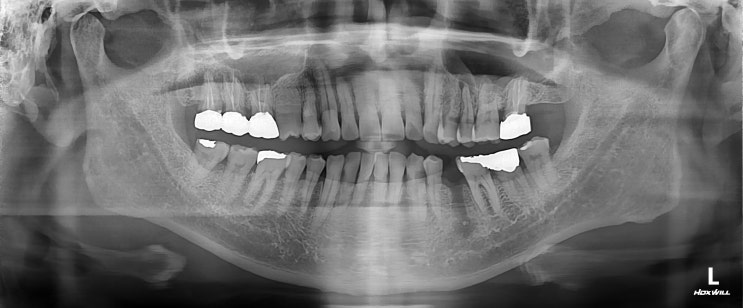

안녕하세요 수서역치과 문정도 치과 수서서울삼성치과 원장 이재현입니다 오늘은 신경치료 후 회복한 환자...